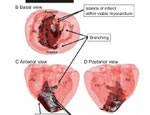

Dr. med. St. Steiner, medizinischer Berater des Bundesverbands, Jahrestagung 2012

Elektrische Implantate bei Herzinsuffizienz (Herzschwäche)